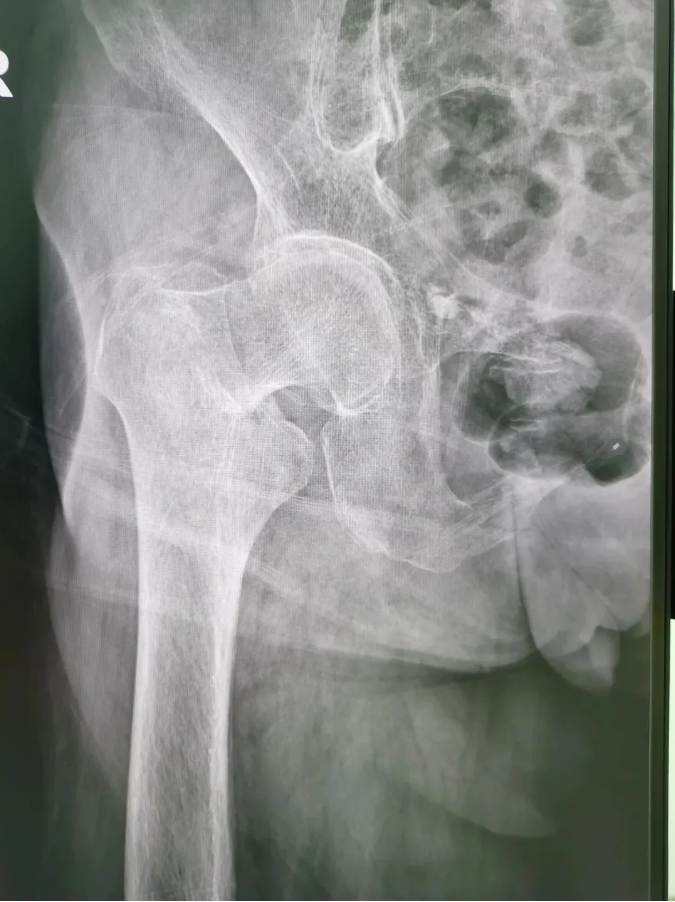

ÊõǰX¹â

½ñÄê91ËêµÄ³ÂÆÅÆÅ£¬9Ô·ÝʱÔÚ¼ÒʧÉ÷ˤµ¹£¬ÓÒÍβ¿×ŵأ¬µ±Ï¸ÐÓ¦÷Ų¿Ç¿ÁÒÌÛÍ´²¢Ô˶¯ÊÜÏÞ¡£ÎªÇó½øÒ»²½ÖÎÁÆ£¬µ½Ë³µÂÇå¾²Íâ¿ÆÒ½Ôº¹ÇÈýÇø¾ÍÕ¸ÃÇøÖ÷ÈÎÑîÉýƽÖ÷ÈÎΪÆäÕïÁÆ£¬±»Õï¶ÏΪ¡°ÓҹɹǾ±¹ÇÕÛ¡±£¬Ðè¾ÙÐÐÓҹɹǾ±¹ÇÕ۾Ƥ±ÕºÏ¸´Î»¿ÕÐÄÂݶ¤ÄÚÀο¿ÊÖÊõ¡£